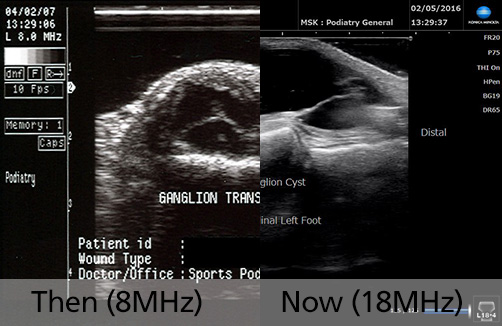

Then (2007) & Now (2020)

8MHz vs 18MHz

• Image 3: Ganglion Cyst